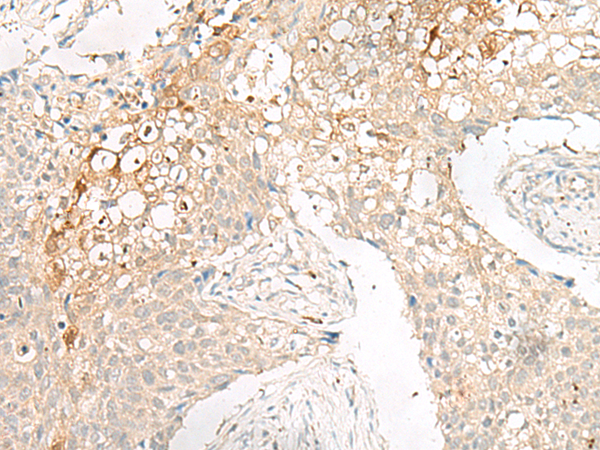

分类: 科研抗体货号: P06583别名: GP210; POM210应用: IHC反应种属: Human, Mouse, Rat